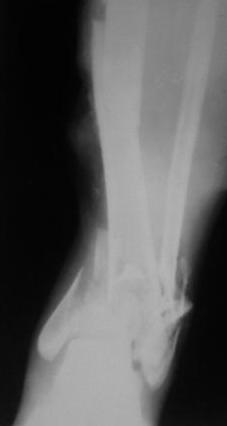

Открытый перелом 43.С3.3

Больной 41г переведен из ЦРБ, травма в результате ДТП- 5 дней назад, произведена ПХО раны, наложена гипсовая повязка.

Об-но; начиная с с/з голени продольно - почти циркулярная рана, с признаками инфицирования - покраснение, отечность, усиление боли, местная т-ра и мутные кровянистые выделения из раны, и выраженная деформация голени. В отд нашей коллегой в экстренном порядке в задней поверхности голени щвы распушены, выпушено около 50мл мутной гематомы, АВФ, умеренная дистракция, антибиотики, и т.д.

Наш план; после устранения воспалительных процессов, перемонтаж аппарата, репозиция оставшихся смещений спицами с упорной плошадкой и стабилизация аппарата, дальше по обстановке.